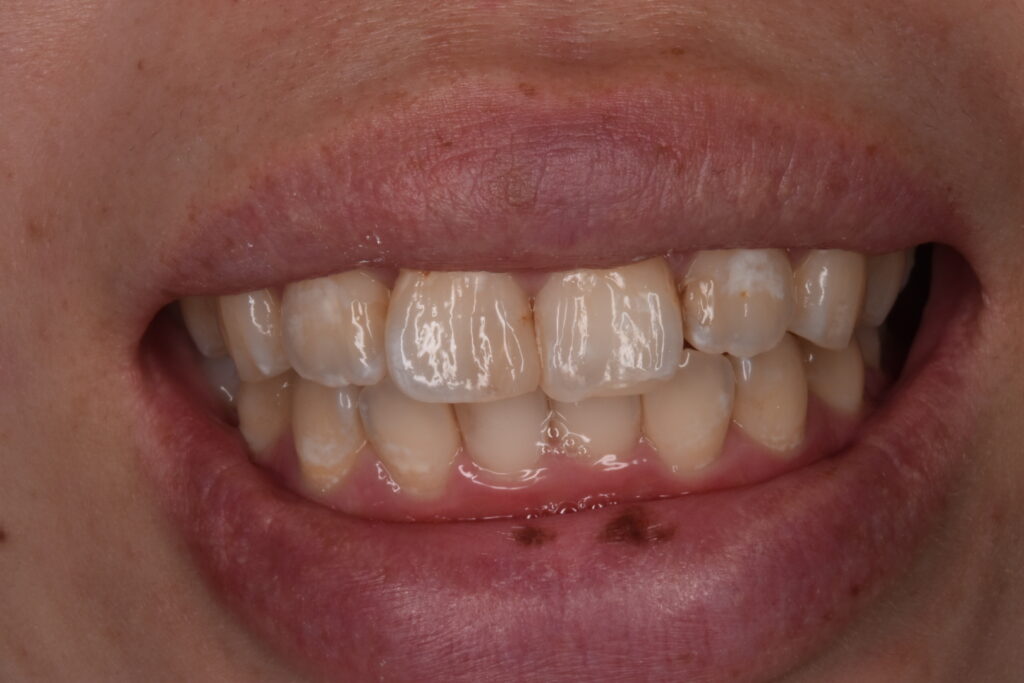

矯正後

矯正はインビザライン モデレートで行っています。追加アライナーなし 途中妊娠出産のため来院間隔が空いています。